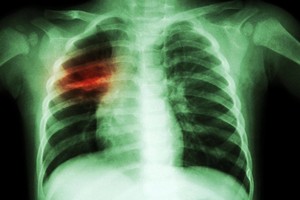

Medikė pabrėžė, kad labai svarbu steigti būtent tuberkuliozei gydyti skirtus stacionarus, kurių palatose negulėtų daugiau nei 2 asmenys. Taip pat šiuo metu tobulinami ambulatorinio gydymo metodai. E.Davidavičienė pabrėžė, kad atvira ligos forma sergantys pacientai turėtų būti izoliuoti nuo visuomenės, kol tyrimai neįrodys, jog visiškai pasveiko. Ypač daug atvira plaučių tuberkulioze sergančių asmenų yra tarp buvusių kalinių, kurie neretai nebaigia pradėto gydymo.

Europos Sąjungos nustatytas sergamumo vidurkis 100 tūkst. gyventojų yra 11 atvejų. Lietuvoje šis skaičius yra net 4 kartus didesnis ir siekia 45 atvejus 100 tūkst. gyventojų. Kaip teigė gydytoja E.Davidavičienė, šie skaičiai jau kelerius metus negerėja, nors PSO reikalavimuose skelbiama, kad kiekvienais metais susirgimų skaičius mažėtų 5 proc.

Tai patvirtino ir pastarųjų kelerių metų bakteriologiniais tyrimais patvirtintų tuberkuliozės atvejų skaičius. Lietuvoje 2012 metais šia liga sirgo 983 asmenys (33 atvejai 100 tūkst.), 2013 m. – 1006 asmenys (34 atvejai 100 tūkst.), 2014 m. – 944 (32,1 atvejis 100 tūkst.), 2015 m. – 894 (31 atvejis 100 tūkst.), o 2016 m. sirgo 880 (apie 30 atvejų 100 tūkst. gyventojų).